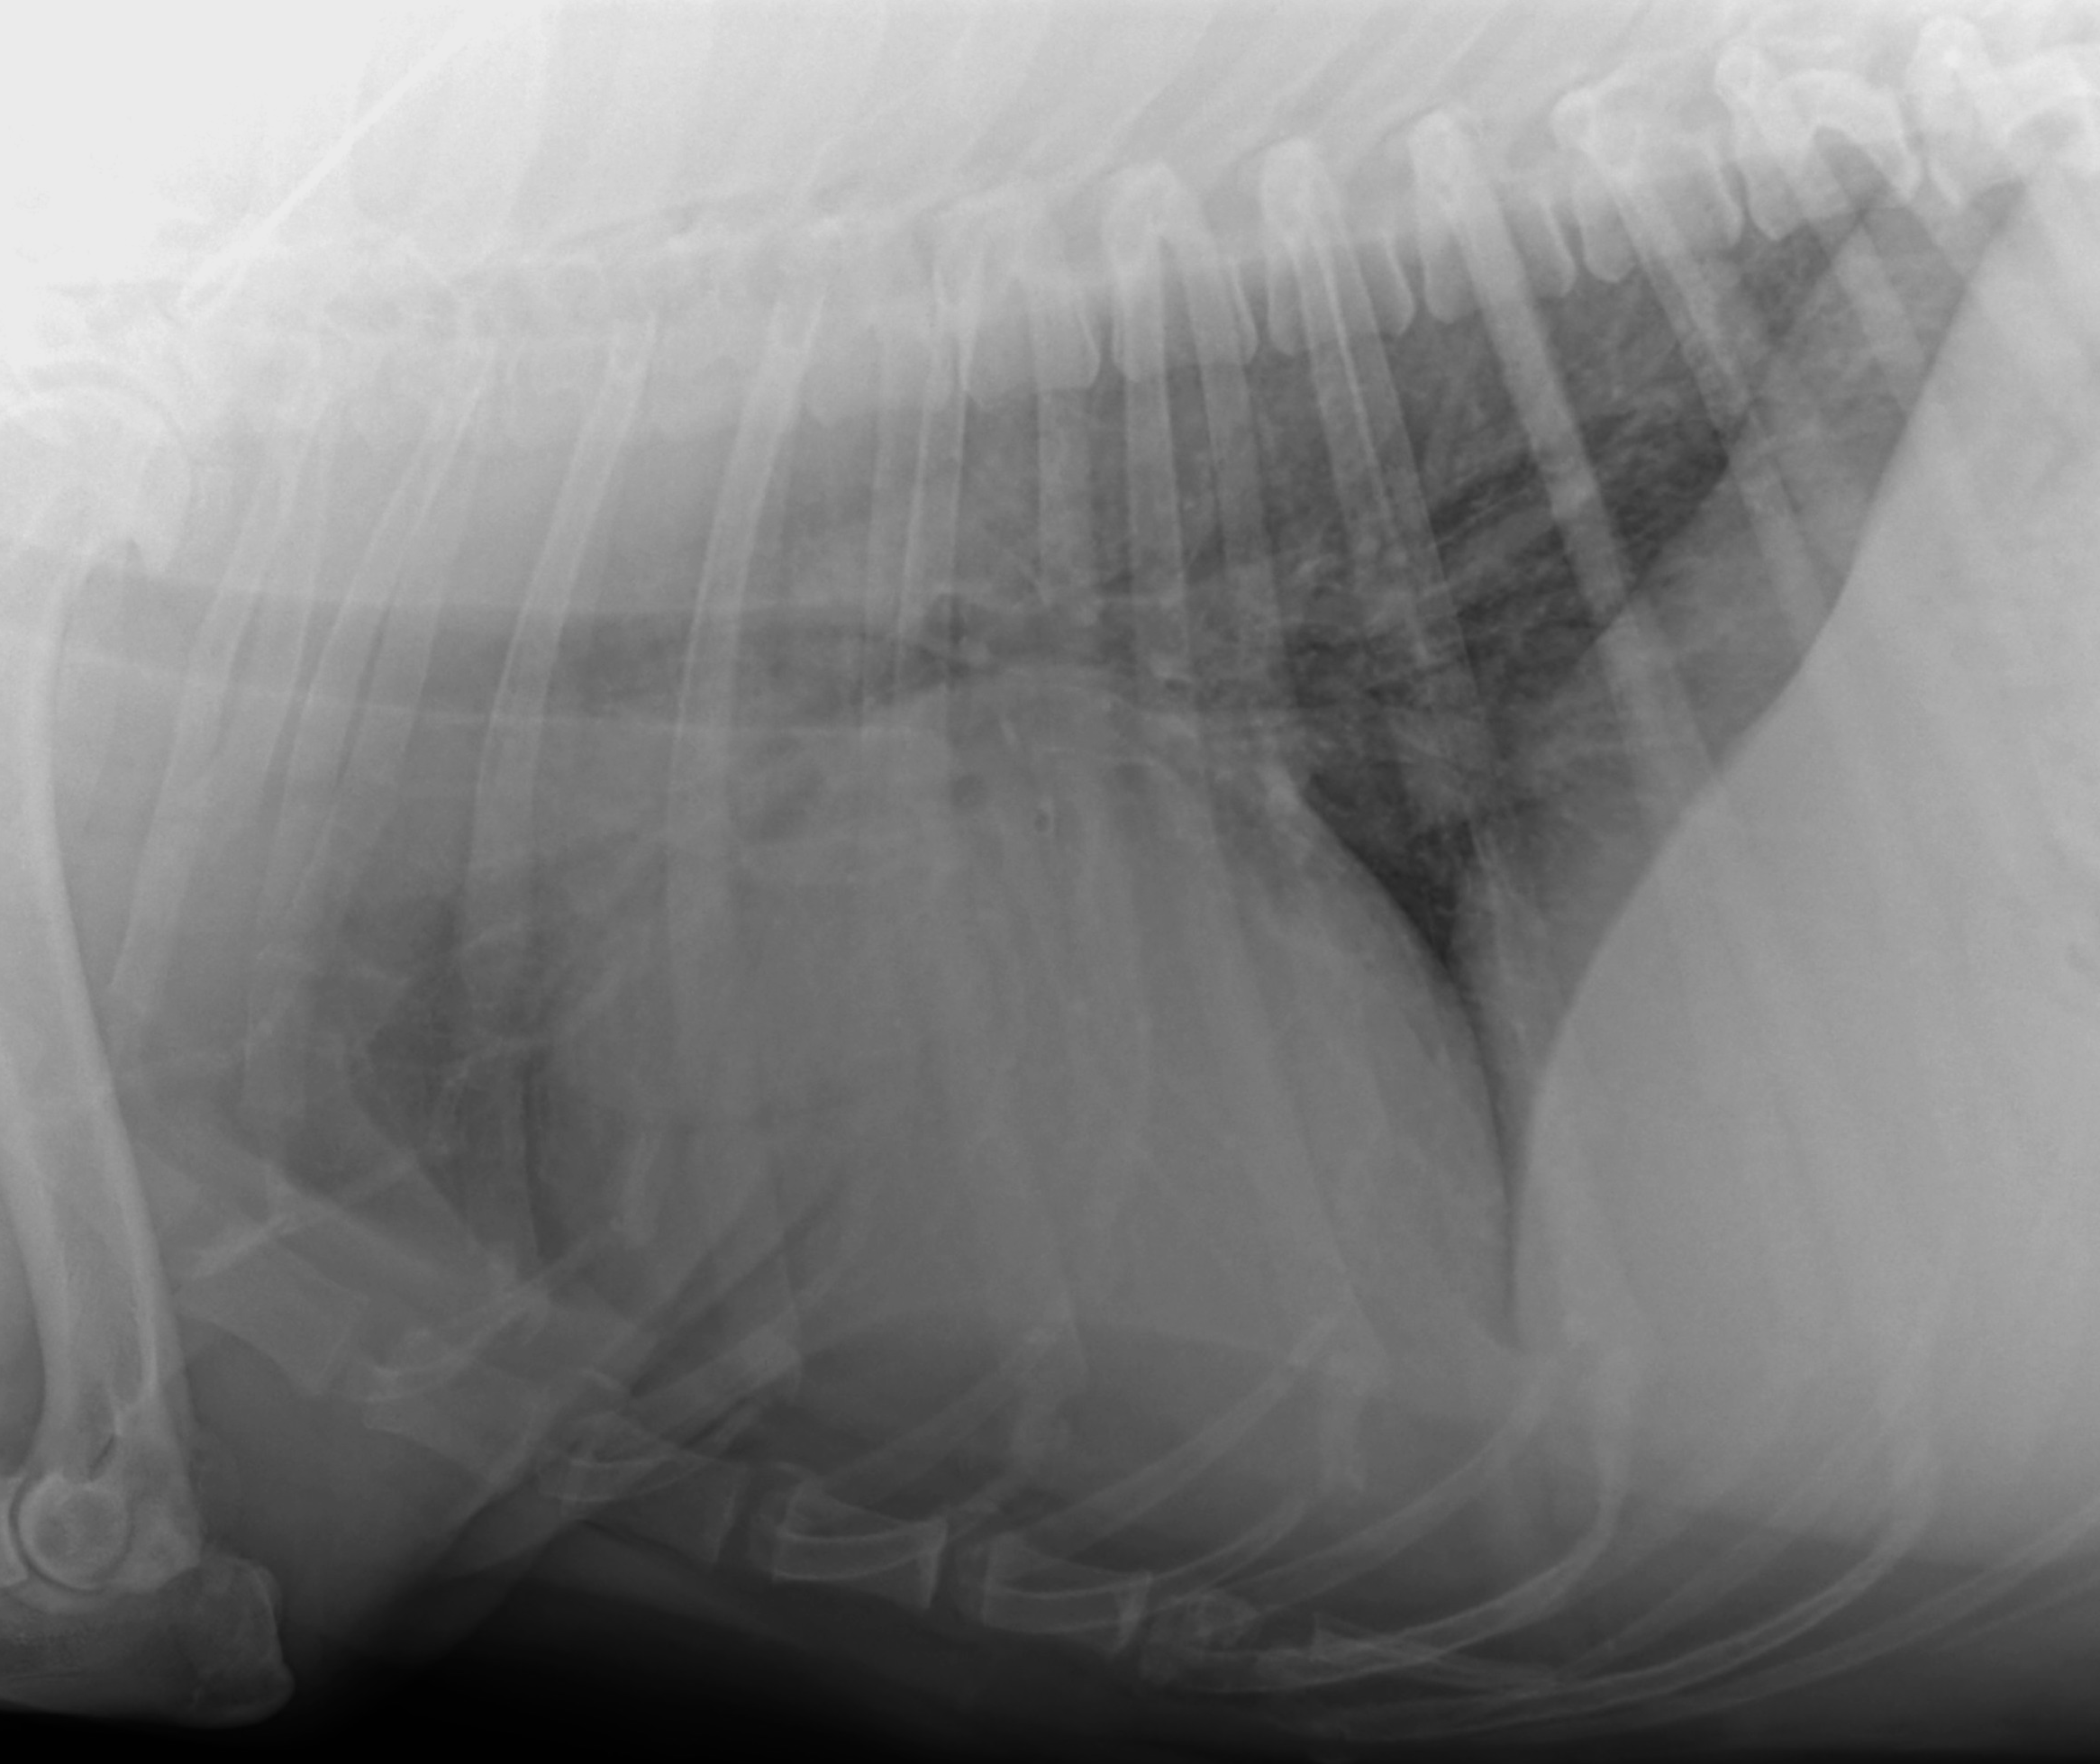

Non convinti? Ok, altro esempio. Vi allego l’immagine del torace di una meticcia Labrador di 9 anni che tossisce. E’ stata eseguita solo una proiezione, con la paziente sedata. Sembrerebbe un decubito laterale destro, ma in realtà è un decubito sinistro, solo che a causa della sedazione e del fatto che la paziente è rimasta per 20 minuti sdraiata sul lato destro, i lobi destri sono completamente atelettasici. Per questo motivo la curva diaframmatica destra è dislocata cranialmente e i polmoni che risultano poveri di aria, risultano molto radio-opachi. Per quale motivo Sugar tossisce?

Passato un mese la paziente continua a tossire ed ha perso quasi sette chili nonostante l’appetito sia quasi conservato. Che fare? Si ripete l’esame radiografico, questa volta con la paziente non sedata.

Come? Non credete che sia la stessa paziente? Controllate l’artrosi nelle spalle e nei gomiti e controllate le alterazioni delle giunzioni costo-condrali e l’ottava sternebra: non ci possono essere dubbi che sia la stessa paziente. L’aver perso 7 kg cambia completamente la radiopacità del polmone e anche il fatto che ora il polmone è completamente areato aiuta molto. Notate niente? Forse un mal definito aumento di pattern interstiziale a livello dei campi dorso-caudali? Che cosa faresti adesso? Che ne dite delle altre due proiezioni?